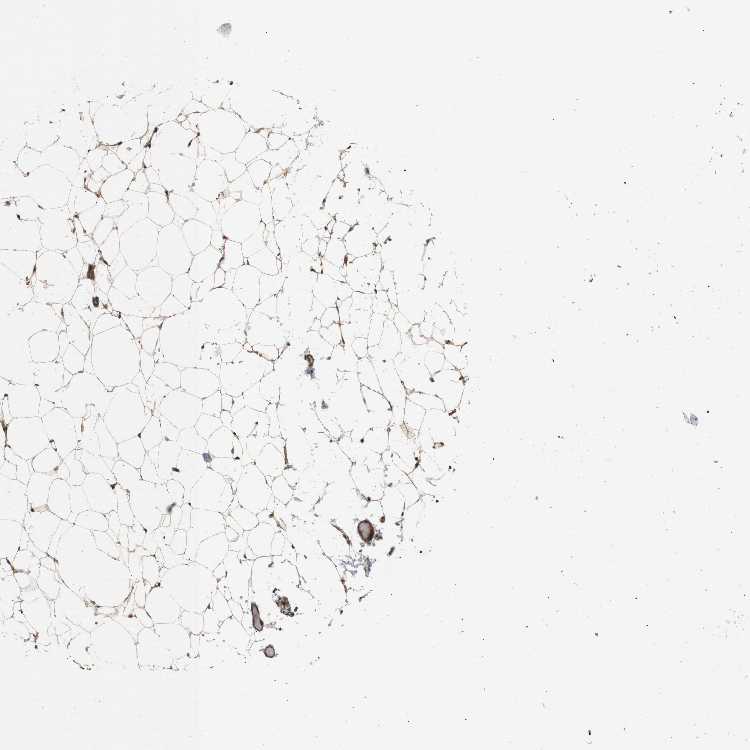

SOFT TISSUE 2 - Antibody stainingi

Antibody staining in the annotated cell types in the current human tissue is reported as not detected, low, medium, or high, based on conventional immunohistochemistry profiling in selected tissues. This score is based on the combination of the staining intensity and fraction of stained cells.

Each image is clickable and will lead to virtual microscopy that enables deeper exploration of all samples and also displays staining intensity scores, fraction scores and subcellular localization as well as patient and tissue information for each sample.

Antibody CAB013514

Fibroblasts Medium

Peripheral nerve Medium